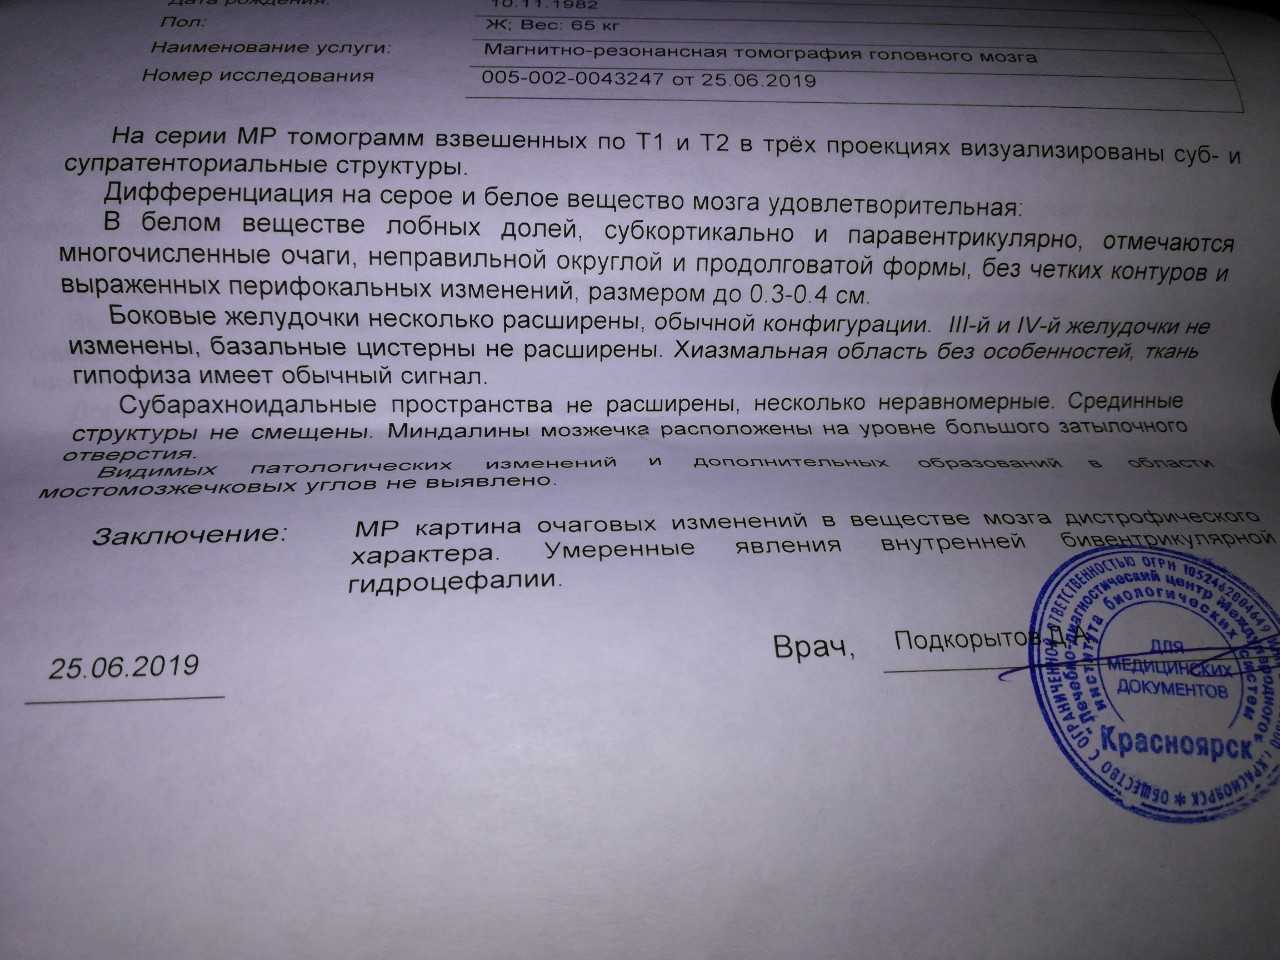

МРТ головного мозга: Расшифровка снимков и Интерпретация

Раздел: Визуальные уроки